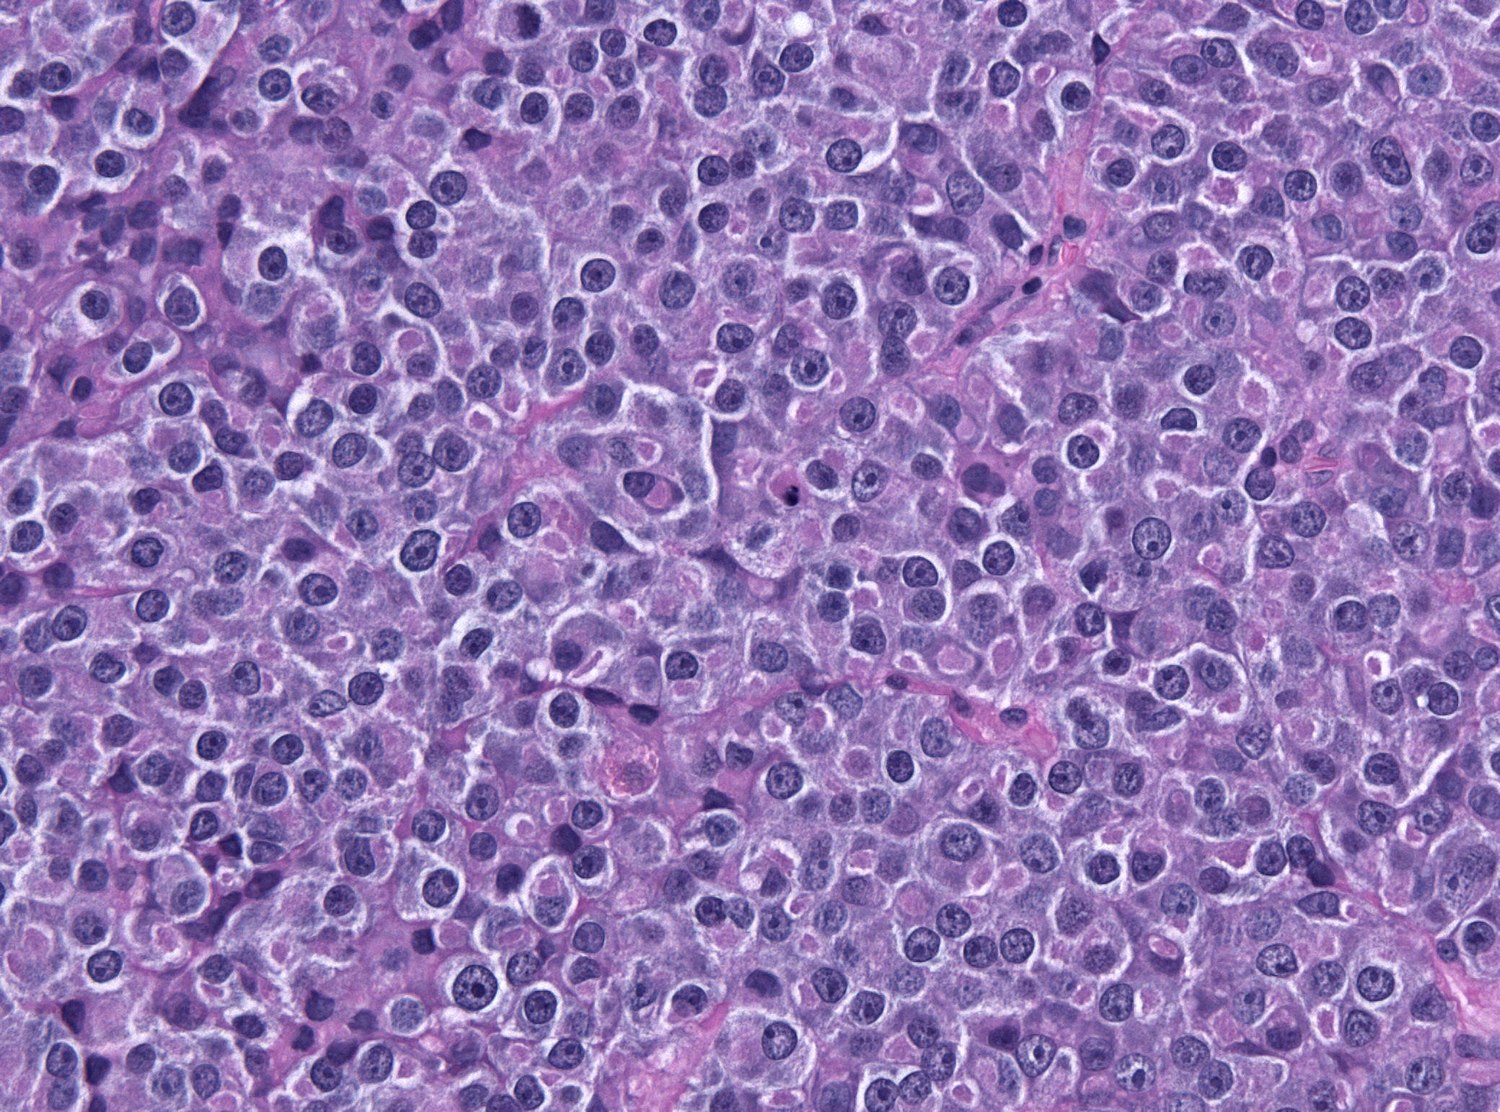

The biopsy revealed dense proliferation of atypical cells with the following characteristics:

- Uniform size

- Prominent nucleoli

- Irregular nuclear borders

These findings led to a diagnosis of diffuse non-Hodgkin’s lymphoma of intermediate size, B-cell type. This histological classification is consistent with the most common subtype of primary bone lymphoma.